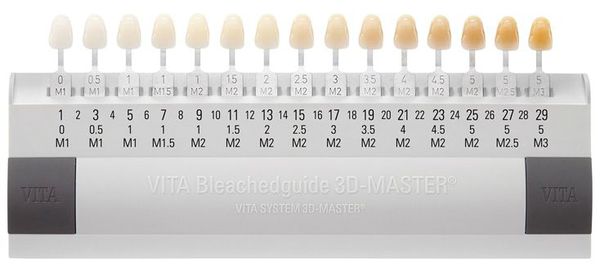

Metoda fotograficzna jest jednym z nowoczesnych narzędzi diagnostycznych stosowanych w stomatologii estetycznej. Umożliwia dokładną ocenę koloru, przezroczystości i ogólnego wyglądu zębów, co ma kluczowe znaczenie przy planowaniu rekonstrukcji lub zabiegów kosmetycznych.

Dzięki specjalistycznym urządzeniom, takim jak Shade Scan, możliwe jest precyzyjne określenie naturalnego odcienia szkliwa. Dane te pozwalają na idealne dopasowanie materiałów używanych do odbudowy zębów – wypełnień, licówek, koron czy mostów.

Do oceny barwy zębów stosuje się palety kolorystyczne, które umożliwiają standaryzację wyników. Najczęściej używana w praktyce klinicznej jest skala Vita Classical, obejmująca 16 odcieni podzielonych na cztery główne grupy – od jasnożółtych, przez neutralne, po szarobrązowe tony.

Takie podejście pozwala stomatologowi dobrać odpowiedni kolor materiału protetycznego lub kompozytu, dzięki czemu efekt końcowy jest naturalny, harmonijny i estetycznie dopasowany do pozostałych zębów pacjenta.